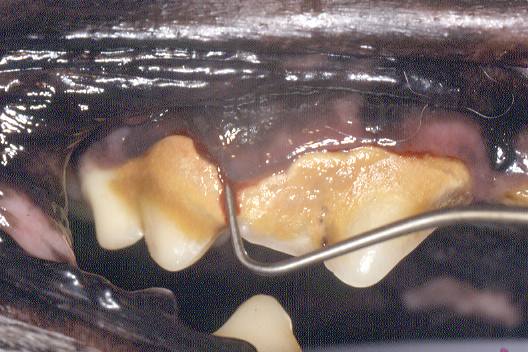

Supra-bony pocket

This pocket is common in dogs and cats. The periodontal tissues migrate apically and probing will reveal an increase in depth from the normal anatomical sulcus.

The entire pocket is coronal to the alveolar crestal bone and within soft tissue. Attachment loss will vary in severity but, in most cases, the pocket will be bound by necrotic cementum on the root surface and chronically inflamed gingiva.

Probe indicates 6-7mm pocket